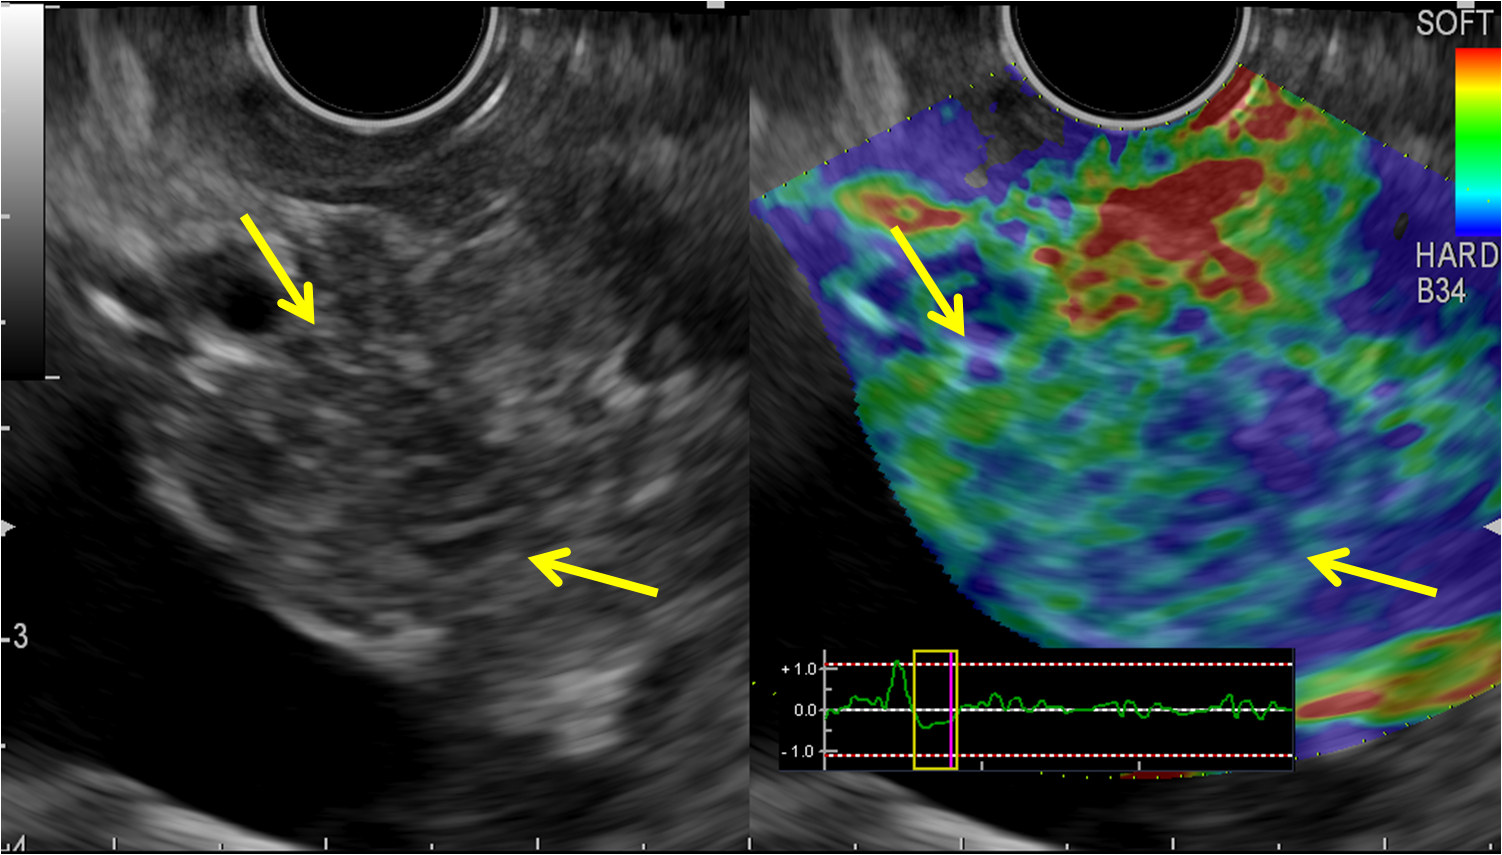

6. ЭУС - эластография различных новообразований поджелудочной железы: б - аденокарцинома | |